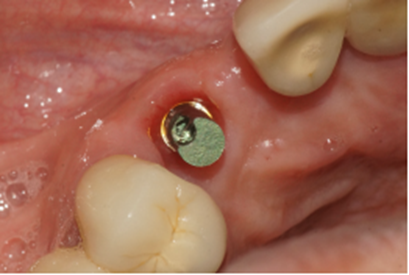

Após 90 dias da instalação do implante, o cicatrizador foi removido e fazendo uso do Kit de Seleção de Componentes da mesma empresa, foi selecionado um pilar Ideale angulado de 3.3 X 4.0 X 1.5 de 17°. Essas mediadas se referem ao diâmetro, altura protética, altura do transmucoso e ao ângulo do pilar, respectivamente (Figuras 9, 10 e 11).

Figura 9 – Cicatrizador removido após 90 dias